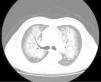

A 51-year-old male presented with a dry cough and mild dyspnoea which had lasted four days. He was a financial consultant, a heavy smoker and had a history of chronic sinusitis but without any prescribed medication. The physical examination revealed no signs of respiratory distress, a bilateral blood pressure (BP) of 220//130mmHg, and left basal crackles. An echocardiography revealed signs of mild aortic, mitral and tricuspid regurgitation and a chest X-ray showed bilateral perihilar “butterfly pattern” alveolar infiltrates. Blood tests showed severe renal failure, hypokalaemia and normocytic anaemia (creatinine: 8.02mg/dL (reference values (RV): 0.72–1.18), potassium: 2.0mmol/L (RV: 3.5–5.1), haemoglobin: 11.2g/dL (RV: 13.0–17.0)). Laboratory coagulation tests were normal (prothrombin time: 16.2s (RV: 12.0–17.4), prothrombin 77% (RV: 70–120)). An arterial blood gas analysis showed respiratory alkalosis with a PaO2 level of 63mmHg (RV 83–108). A non-contrast chest CT found bilateral central parenchymal infiltrates with a “crazy paving” pattern (Fig. 1) and a renal ultrasound found bilateral increased kidney echogenicity with preserved size. A bronchoscopy with bronchoalveolar lavage was performed, and progressively bloody fluid was retrieved. Urinalysis showed microscopic haematuria and proteinuria (+++) with a spot urine sample protein to creatinine ratio of 2380mg/g (RV: <200). Fundoscopic examination identified signs of hypertensive optic neuropathy, and the patient was admitted for malignant hypertension, under aggressive anti-hypertensive therapy. He remained stable and the pulmonary infiltrates improved, but poor renal function and difficult hypertension continued. Further study revealed cytoplasmic iron deposits in alveolar macrophages with a moderate alveolar haemorrhage but no signs of pulmonary infection. The auto-immune panel was negative, including anti-nuclear antibodies, proteinase-3-antineutrophil cytoplasmic antibodies, myeloperoxidase-antineutrophil cytoplasmic antibodies, anti-glomerular basement membrane antibodies, cryoglobulins and rheumatoid factors. Complement levels were normal and viral serologies were negative. The plasma renin was 1090μU/ml (RV: 7–76), aldosterone was 5660pg/ml (RV: 30–310), and aldosterone to renin activity ratio was 6.3ng/ng (RV: 14.5). An abdominal CT scan revealed a left adrenal nodule and a renal eco Doppler excluded renal artery stenosis. An ultrasound guided kidney biopsy was performed revealing hypertensive nephroangiosclerosis with chronic interstitial nephritis and arterio-sclerosis and arteriolo-sclerosis. There was no evidence of active necrotizing glomerulonephritis, crescent formation, immune deposits or vasculitis. The procedure was complicated by late bleeding and renal haematoma requiring embolization of the left renal artery. After the embolization, normalization of blood pressure and potassium levels were noted. A new evaluation of plasma renin and aldosterone levels showed normal results. The patient became asymptomatic; there was complete resolution of pulmonary infiltrates and hypoxaemia, but no recovery of renal function, requiring chronic haemodialysis. The final diagnosis was probable adrenal reninoma, leading to malignant hypertension, diffuse alveolar haemorrhage and chronic renal failure.